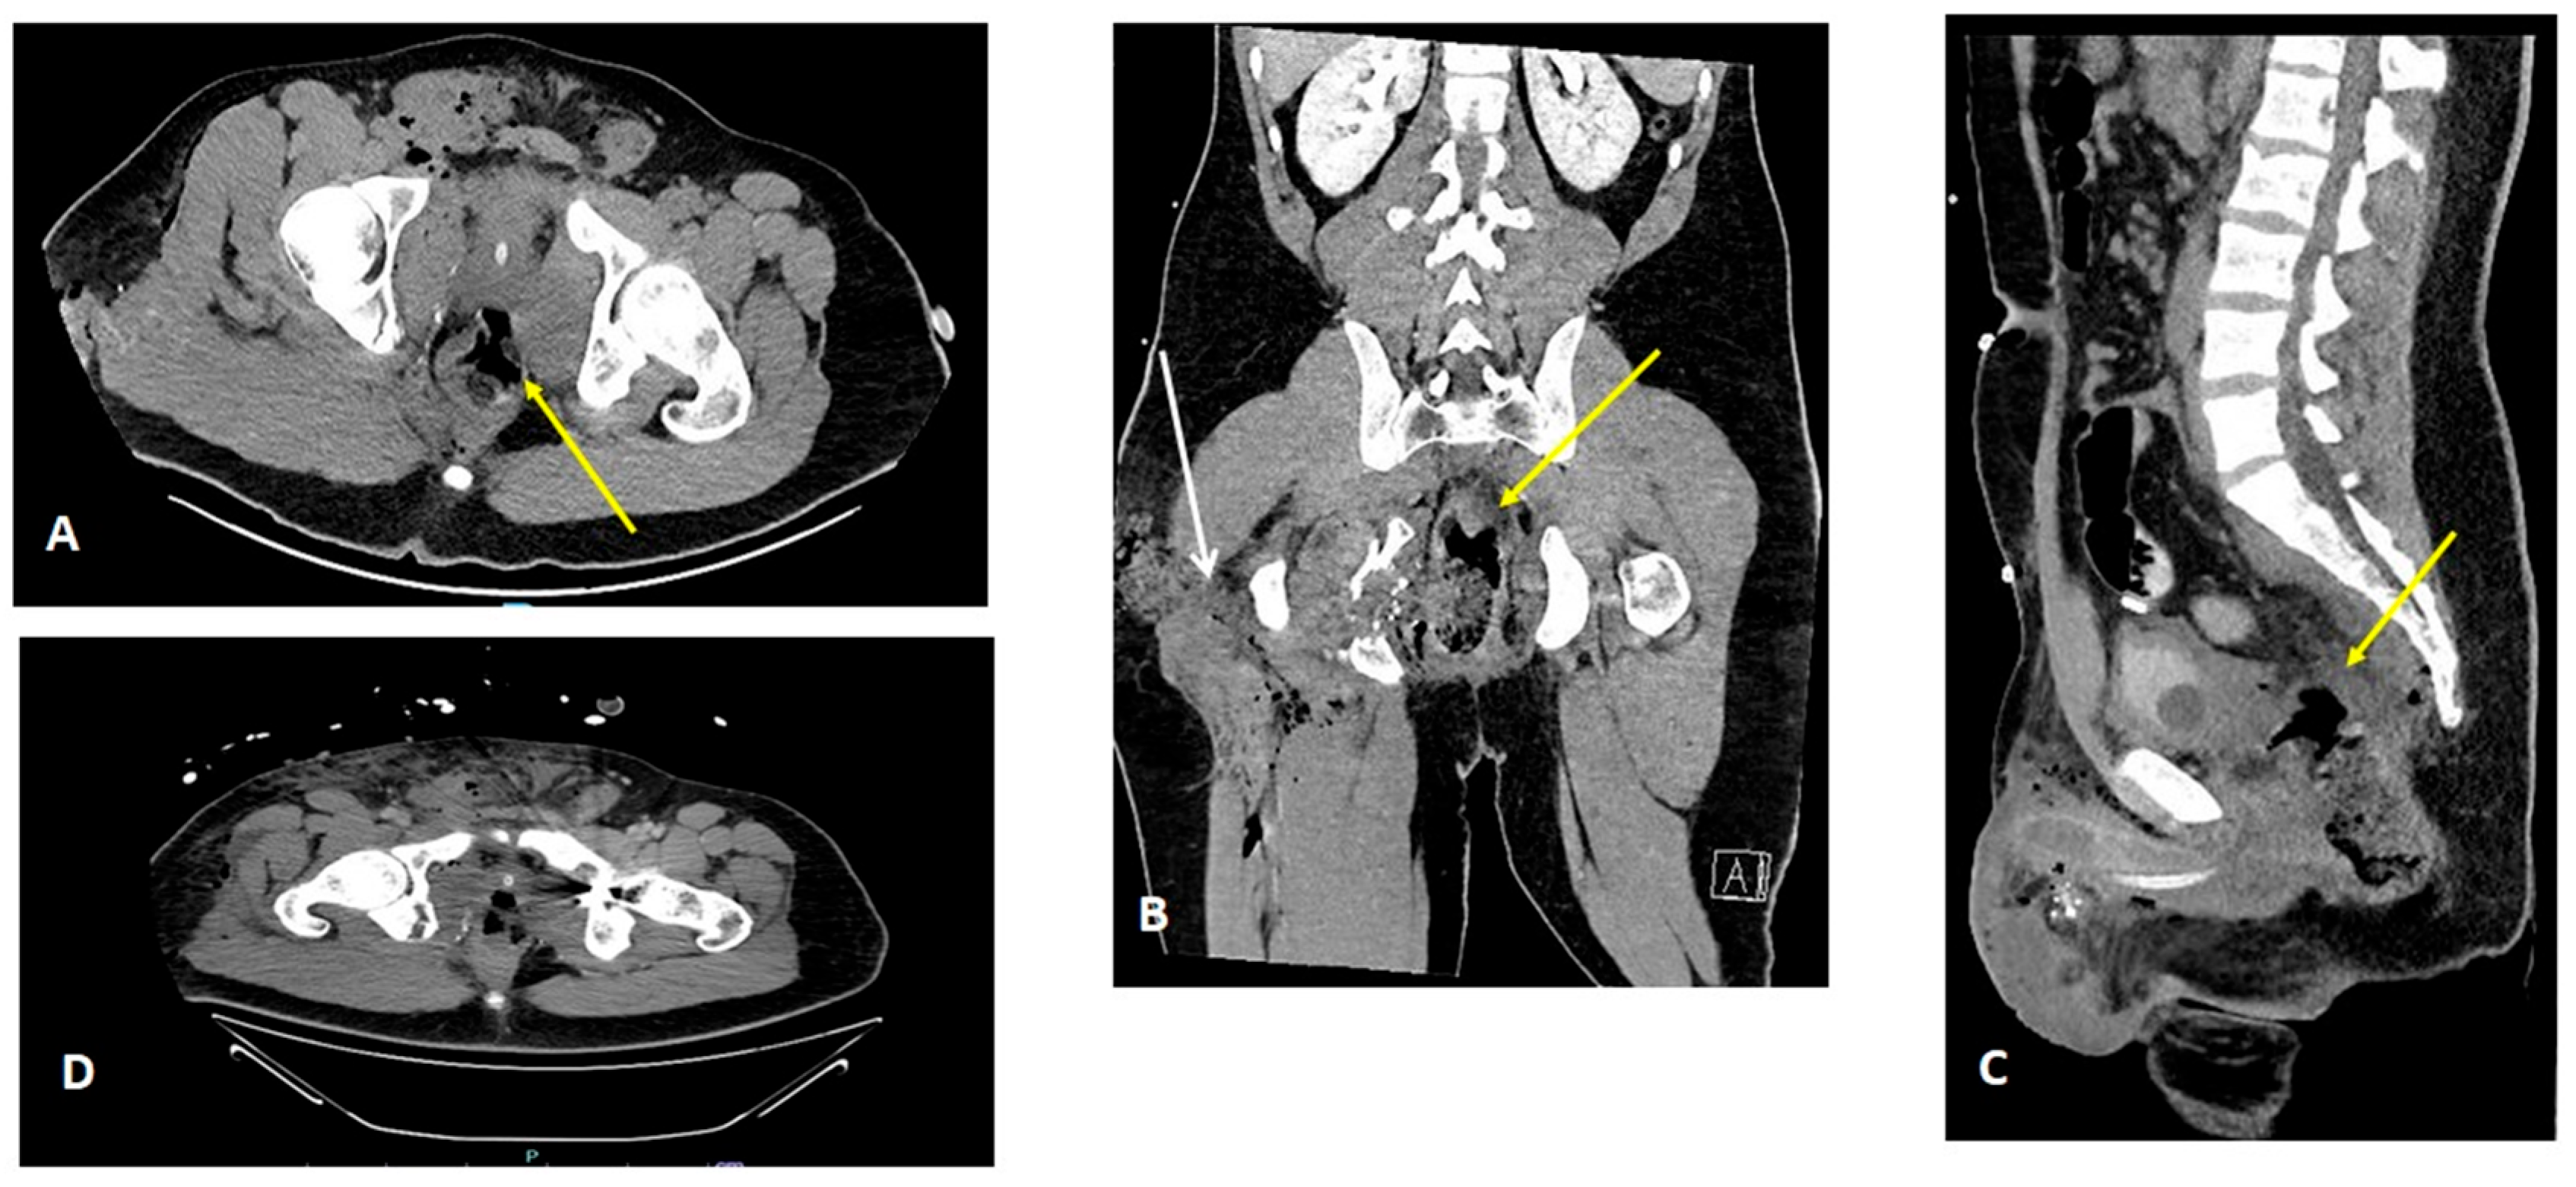

2. Detailed Case Description